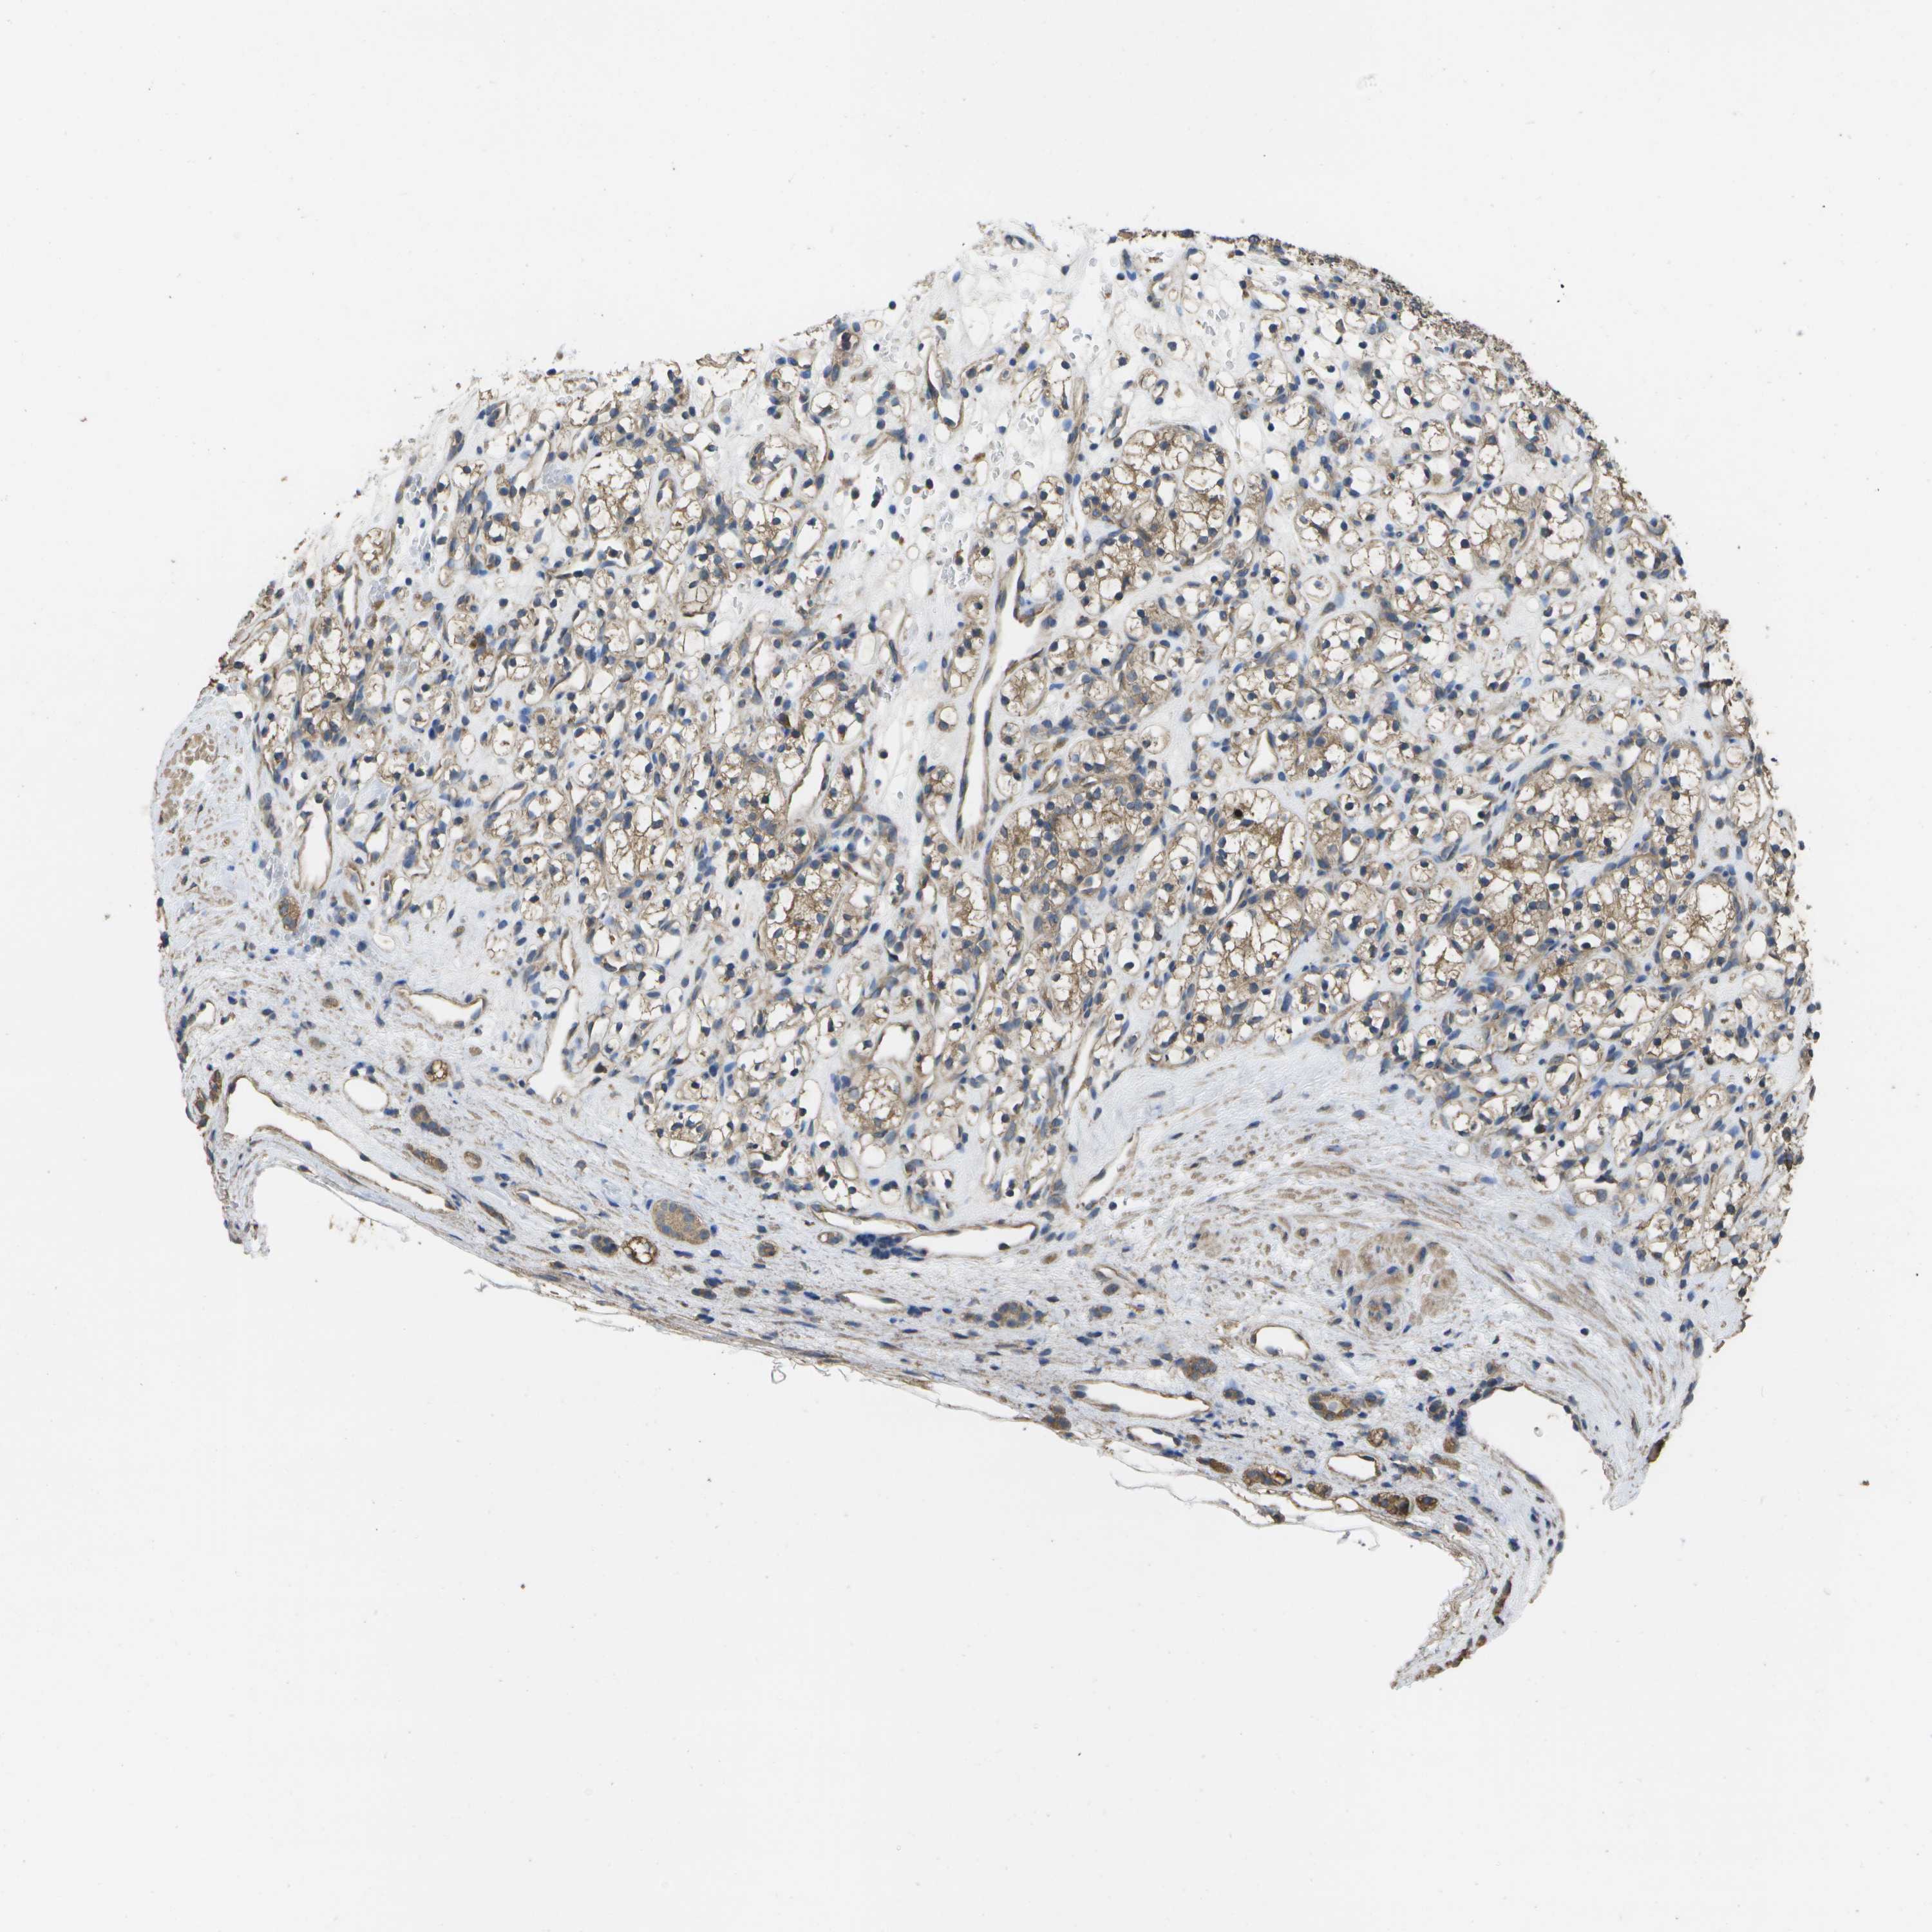

KIDNEY RENAL PAPILLARY CELL CARCINOMA (TCGA) - Interactive survival scatter ploti

The Survival Scatter plot shows the clinical status (i.e. dead or alive) for all individuals in the patient cohort, based on the same data that underlies the corresponding Kaplan-Meier plots. Patients that are alive at last time for follow-up are shown in blue and patients who have died during the study are shown in red.

The x-axis shows the expression levels (FPKM) of the investigated gene in the tumor tissue at the time of diagnosis. The y-axis shows the follow-up time after diagnosis (years). Both axes are complimented with kernel density curves demonstrating the data density over the axes. The top density plot shows the expression levels (FPKM) distribution among dead (red) and alive patients (blue). The right density plot shows the data density of the survived years of dead patients with high and low expression levels respectively, stratified using the cutoff indicated by the vertical dashed line through the Survival Scatter plot. This cutoff is automatically defined based on the FPKM cutoff that minimizes the p-score. The cutoff can be changed by dragging the vertical line or by entering a cutoff value in the square labeled "Current cut-off".

Under the Survival Scatter plot the p-score landscape (black curve; left axis) is shown together with dead median separation (red curve; right axis). Dead median separation is the difference in median mRNA expression between patients who have died with high and low expression, respectively. It is calculated as follows: median FPKM expression of dead patients with high expression - median FPKM expression of dead patients with low expression. This is intended to aid the user in visually exploring custom cutoffs and the associated p-scores and dead median separation.

Individual patient data is displayed and can be filtered by clicking on one or more of the category buttons on the top of the page. Categories describing expression level and patient information include: high, low, alive, dead, female, male and tumor stages. The scale of the x-axis can be toggled between linear and log-scale by clicking on the "x log" button. Mouse-over function shows TCGA ID, patient information and mRNA expression (FPKM) for each patient.

& Survival analysisi

Kaplan-Meier plots summarize results from analysis of correlation between mRNA expression level and patient survival. Patients were divided based on level of expression into one of the two groups "low" (under cut off) or "high" (over cut off). X-axis shows time for survival (years) and y-axis shows the probability of survival, where 1.0 corresponds to 100 percent.

SACS is not prognostic in Kidney Renal Papillary Cell Carcinoma (TCGA)

Best expression cut offi

Based on the FPKM value of each gene, patients were classified into two groups and association between prognosis (survival) and gene expression (FPKM) was examined. The best expression cut-off refers the FPKM value that yields maximal difference with regard to survival between the two groups at the lowest log-rank P-value. Best expression cut-off was selected based on survival analysis .

When clicking on this number, the vertical dashed line indicating cut-off, the interactive survival plot, and the Kaplan-Meier curve will be adjusted to show results based on the best expression cut-off.

: 1.35